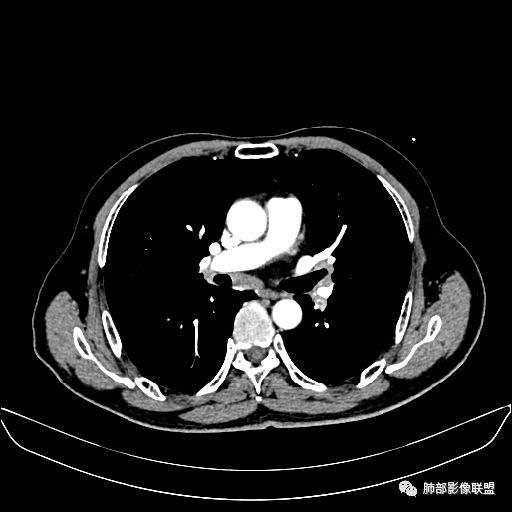

住院4天后行胸部增强CT

动脉期

老年男性,因“咳嗽咳痰1月余。”入院。病程中咳嗽咳痰,咳黄白痰,间断咯少许鲜红色痰血。PPD阳性。胸CT:右肺中叶外侧段支气管管腔阻塞,大片实性病变,病灶边缘光滑,部分边缘膨隆,可见分叶,肺门及纵隔可见肿大淋巴结,并可见钙化。增强可见病灶明显强化,而且延迟强化明显,病灶内多发低密度区,内见血管影,血管变细、部分血管破坏。考虑恶性病变可能性大,鉴别慢性肉芽肿性病变。

胸CT:跨叶大肿块,主体在中叶,右中叶外侧段支气管阻塞,病灶部分边缘膨隆,可见分叶,部分边缘平直,肺门及纵隔可见肿大淋巴结。增强病灶不均匀强化,延迟强化明显,病灶内多发低密度区,内见血管飘浮,部分血管变细、模糊。考虑:恶性病变可能性大,大细胞?淋巴瘤?鉴别慢性肉芽肿性病变。

右肺中叶软组织肿块,外围向内生长,叶间胸膜向前内移位,肿块近肺门侧跨叶,中叶外侧段支气管截断,密度不均匀,双侧肺门及隆突下见肿大淋巴结,增强后呈中度不均质强化,肺动脉供血,多发坏死区,边界尚清,坏死区域内见结构,结合病史考虑恶性,鉴别诊断1结核,爬行征是沿支气管树分布,外宽,内窄,周围有卫星灶,内气管狭窄后扩张,此例沿叶间胸膜长轴分布,气管有截断,不典型。2炎性肉芽肿,符合的地方下方层面增强后延迟性轻度环形强化,不符临床无发热等急性感染病史,实验室指标不符,病灶周围渗出及慢性炎性改变有,不明显。